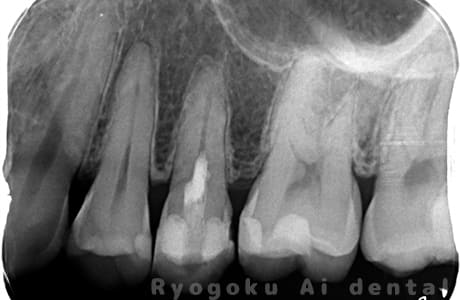

Case04

- 原因

- C3、重度カリエス

-

- 治療内容

- 17・15断髄治療

- 治療費用

- 154,000円

他院で神経をとるほどの虫歯があり、神経を残したいとのことで来院された患者様です。歯の神経を一部分取る断髄治療を行い、問題なく経過を追っています。

<リスク・副作用>

術後は痛み、腫れ、痺れなどの副作用が生じる場合があります。症状が再発する可能性があります。その場合は抜髄する必要があります。